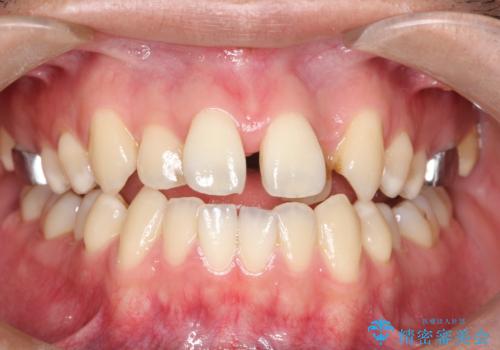

【MSE+インビザライン】前歯のガタガタ

- 前歯の凸凹を主訴に来院されました。

上の歯のアーチが狭窄していたため、骨の幅を広くするためにMSE(急速拡大装置)を使用してからインビザライン にて治療を行いました。

MSE(急速拡大装置)を用いたことで、短期間で奥歯の噛み合わせもしっかりと治すことができました。